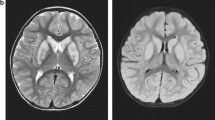

This boy is the first child to healthy unrelated parents of Kurdish origin. Apart from transiently decreased fetal movements reported by the mother (during 7th months of pregnancy), the pregnancy was uneventful. The boy was born after 37 weeks of gestation with a birth weight of 2630 g, length of 49 cm and head circumference of 32 cm. The Apgar score was 10-10-10 and the perinatal period was uncomplicated. The boy was first admitted at 9 months of age because of bilateral esotropia. He was then also found to have hyperopia (+7-8). Regular ophthalmological investigation revealed no other changes. He was again admitted at 13 months of age because of delayed psychomotor development. He could sit, grasp with his whole hands and move between them and babbled with two syllables, corresponding to a developmental age of around 6–7 months. Muscle tone and tendon reflexes were normal. He learned to say a few words and to walk unsupported around 3 years of age. His communicative skills peaked at 5 years of age when he could combine 2–3 words, while his best motor function was at 9 years of age when he could walk unsupported both uphill and downhill. He has since then slowly lost developmental skills and has become increasingly stiff. A trial of L-Dopa treatment had no effect. A permanent gastrostomy was placed at 11 years of age because of swallowing difficulties although he still managed to eat small pieces of food by himself. At the last assessment at 16 years of age, he was a very happy and easy-going young man with the ability to communicate with gestures, sounds, pointing and about 30 signs and a few words. He was able to walk around 100 m with support and had a comparably good fine motor function with bilateral pincer grasp. On examination he had generally increased muscle tone considered to be a mixture of spasticity and rigidity with associated contractures in large joints and a right-sided scoliosis. The muscle tendon reflexes were generally increased with left-sided ankle clonus and a right-sided Babinski’s sign. There were no involuntary movements or signs of ataxia. He had no seizures and EEG was normal. Head circumference and height has been normal and there were no signs of additional organ involvement. Routine laboratory investigations including metabolic screening analyses have been normal. A 3 T MRI of the brain was performed at 8 years of age showing mild features of hypomyelination and thinning of corpus callosum (Fig. 1). In view of the unusual phenotype, further investigation of the SLC17A5 gene was driven by the elevation of free sialic acid in urine and fibroblasts.

Axial T2 sequences showed slightly increased T2 signal in supratentorial central white matter (a) while the cerebellar white matter looked normal (b). Axial T1-weighted imaging showed normally signaling supratentorial white matter (c). Sagittal T2-weighted imaging revealed a somewhat thin corpus callosum and a small cyst (1.2 cm) of the corpus pineale (d)

The lysosomal free sialic acid storage disorders present with a broad clinical spectrum. Salla disease represents the mildest phenotype and occurs most frequently in Finland, and other Nordic countries such as Sweden and Denmark [7, 8, 18, 19]. The infantile form of sialic acid storage disease shows a more severe clinical phenotype and has no geographic predominance [7, 20, 21]. There also exists SASD forms that are intermediate in severity between Salla and ISSD [22–26]. Whereas Salla patients usually present with hypotonia, ataxia and nystagmus the first year of life, our patient showed delayed psychomotor development together with hyperopia at age 3 years. Ataxia usually remains a prominent feature as Salla disease progresses, however in the present case ataxia has not incurred. Instead, our patient shows increased muscle tone, most likely due to a mixture of spasticity and rigidity. The only clinical symptoms overlapping with Salla disease are in fact early psychomotor retardation and speech problems, which by itself is not very disease specific. MRI findings further support the milder clinical phenotype with weak features of hypomyelination and thinning of corpus callosum in contrast to Salla patients where cerebral and cerebellar atrophy, hypomyelination and corpus callosum hypoplasia are typical findings. Thus, the patient described in this paper shows an even milder clinical phenotype of SASD than Salla disease, which makes it difficult to pinpoint the correct diagnosis. Our findings suggest that analysis of free sialic acid needs to be considered in patients with encephalopathy and mild hypomyelination and thinning of corpus callosum.